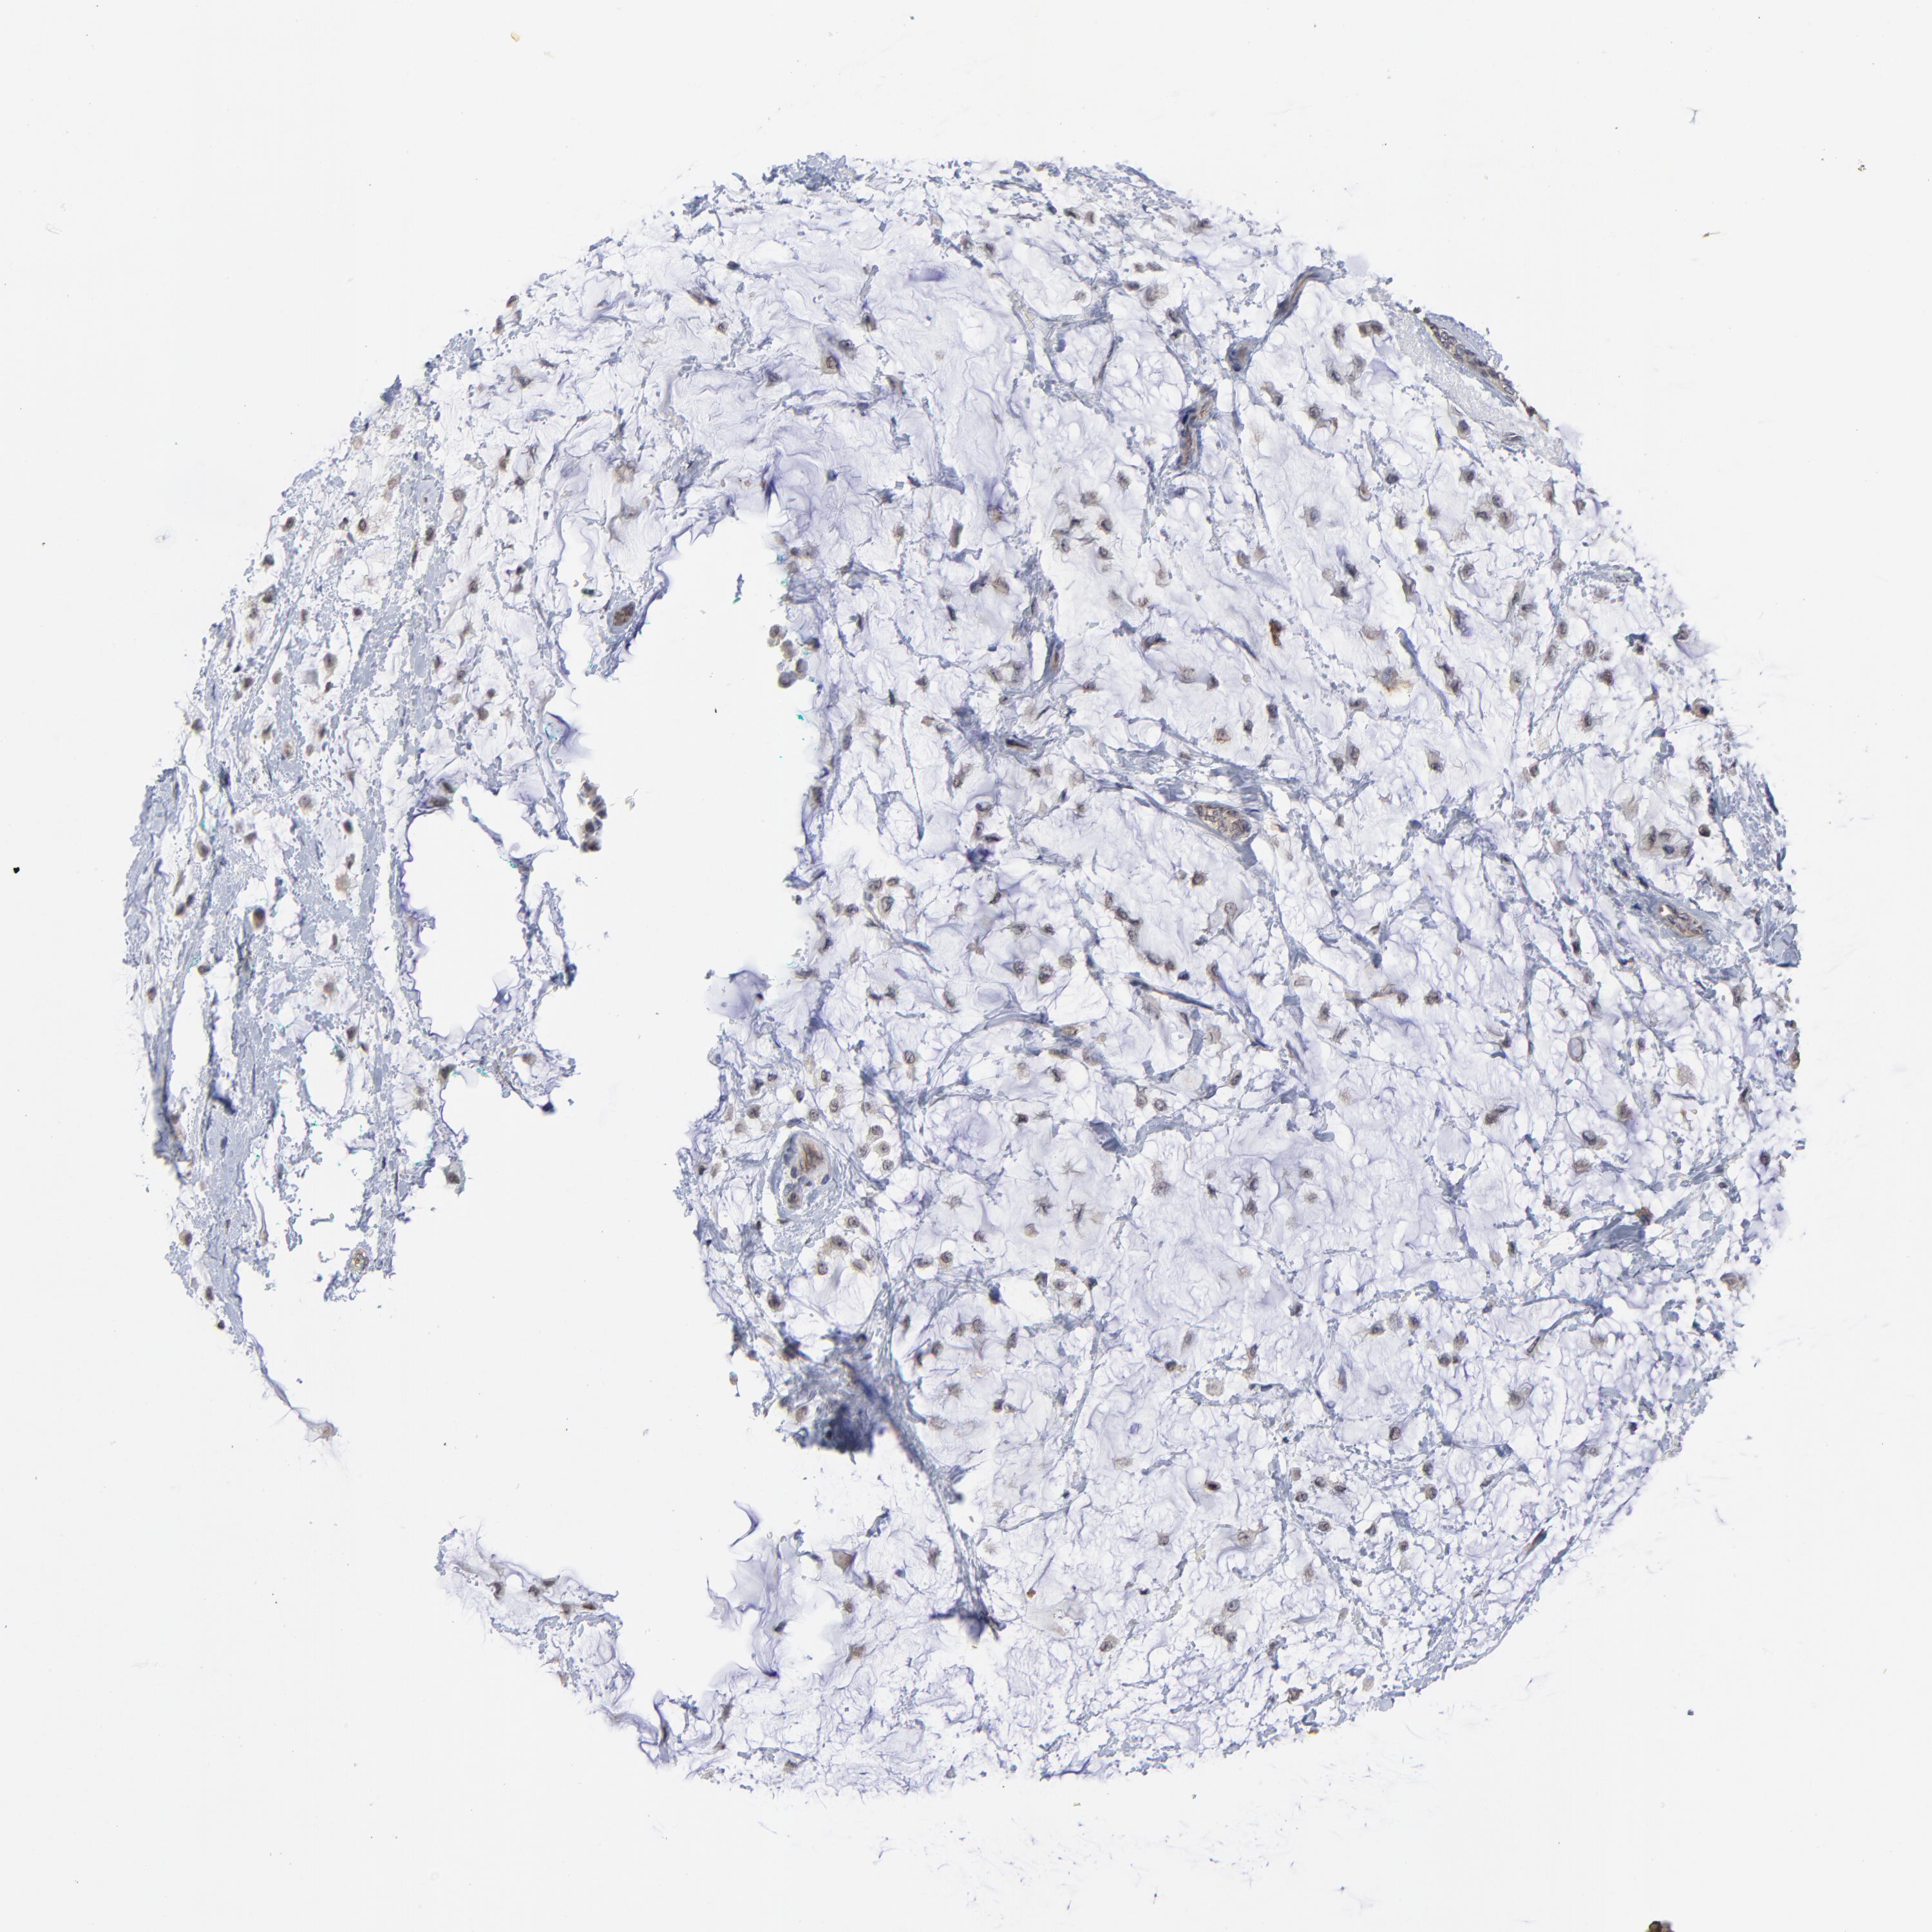

ZNF157

CANCER BREAST CANCER Show tissue menu

BRCA TCGA BRCA VALIDATION PROTEIN EXPRESSION

ZNF157 is not prognostic in Breast Invasive Carcinoma (TCGA)

Average pTPM 0.2

Number of samples 1022